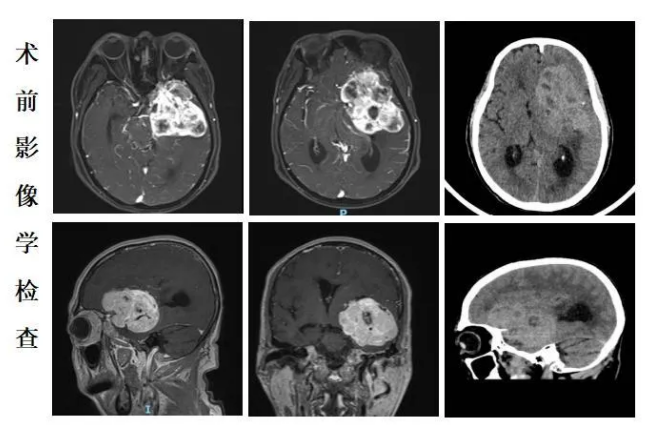

入院时,黄大爷右侧肢体的肌力评级为0级,这意味着他的右手和右脚完全动不了。随后的头部磁共振检查发现,导致这一切的“元凶”,是一个约8×7×6厘米大小的脑膜瘤,体积接近一个成人拳头。长在这个位置、这么大的肿瘤,就像在脑子里埋了一颗不定时“炸弹”。正是肿瘤压迫了大脑的重要功能区,才导致患者半身瘫痪。

面对这一高风险病例,手术成为主要选择,但难度极大。肿瘤位置深、血供丰富,周围密布重要神经和血管,稍有不慎就可能造成严重后遗症。经过充分评估和周密准备,该院神经外科专家团队为黄大爷实施了开颅肿瘤切除手术。手术持续了数小时,医生在“神经丛林”中进行精细操作,最终将肿瘤完整切除,确保病灶被彻底清除。